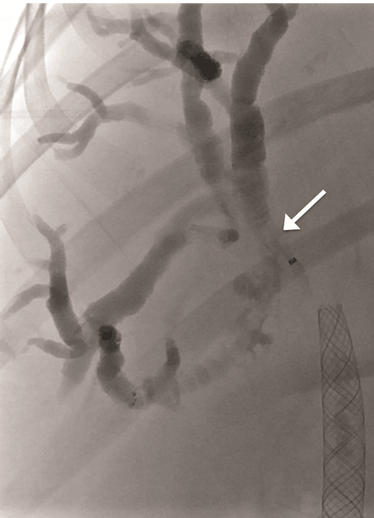

A 52-year-old female presented to her general physician with a four-month history of right upper quadrant discomfort and was referred for an outpatient abdominal ultrasound scan. This revealed intrahepatic duct dilatation and subsequent computed tomography (CT) scan of liver and magnetic resonance cholangiopancreatography (MRCP) confirmed imaging features of a 24-mm intrahepatic cholangiocarcinoma. This was located immediately proximal to the confluence of the left and right hepatic ducts and was causing obstruction of the left intrahepatic ducts. There were no distant metastases identified on imaging or staging laparoscopy. Endoscopic retrograde cholangiopancreatography (ERCP) and direct endoscopy of the bile duct was performed with the aim of directly visualizing the tumor to obtain a biopsy and confirm the diagnosis. Cannulation of the bile duct was difficult and a pre-cut sphincterotomy was performed in an attempt to facilitate access, but this was unsuccessful. The procedure was complicated by a duodenal perforation with retroperitoneal collection and pancreatitis, which delayed definitive management. The tumor was thought to be resectable after initial imaging, but unfortunately, repeat CT scan demonstrated progression over the subsequent weeks with involvement of the right portal vein and right intrahepatic ductal system. The patient was discharged two weeks after the ERCP, but re-presented to the emergency department a week later complaining of abdominal pain and nausea. At this time, she was noted to be clinically jaundiced. Fluoroscopically guided percutaneous trans-hepatic cholangiography (PTC) and bare metal stent insertion was therefore performed under conscious sedation as a palliative procedure to relieve the obstruction. Following puncture of the right anterior ducts with an introducer set ('Accustick' introducer set, Boston scientific®), complete occlusion of the ductal system was demonstrated. There was no cross filling of the left segmental ducts. The obstruction was traversed with a guide wire. A 10x70 mm USEMS (Placehit Biliary WALLSTENT, Boston Scientific®) was then deployed across the stricture and was positioned with 3 cm of stent proximal to the tumor to allow maximum proximal expansion within the duct and ensure optimal flow of bile from the intrahepatic ducts (Figure 1). Free flow of contrast into the common bile duct was demonstrated, indicating successful procedure and no balloon expansion was required. The day after the procedure, the patient complained of abdominal pain and nausea, and developed a temperature of 38.5°C. She was noted to be more jaundiced. Serum bilirubin rose from 84 mmol/L (normal range: 21–100 mmol/L) before the stent placement to 268 mmol/L two days post-procedure. Full blood count revealed elevated white cell count of 21x109/L (normal range: 4–11x109/L) and serum C-reactive protein (CRP) increased to 47 mg/L (normal range: 4–8 mg/L). A diagnosis of biliary sepsis was made. Blood cultures grew Enterococcus faecium with resistance to amoxicillin. Teicoplanin, gentamycin and metronidazole were commenced. The liver function tests failed to improve over the next few days, and a repeat PTC was performed eight days after the first procedure which demonstrated that the stent had slipped through the stricture into the extra-hepatic biliary tree, and that the right intrahepatic duct was once again completely occluded (Figure 2). A wire was placed across the occlusion and through the centre of the migrated stent, and a further uncovered 10x70 mm self-expandable metal stent (Placehit Biliary WALLSTENT, Boston Scientific®) was then placed across the stricture and deployed, the distal end of the new stent sited within the proximal end of the migrated one. There was some wasting in the region of the tumor which was dilated using a balloon dilatation catheter (35LP Low-Profile PTA Balloon Dilatation Catheter (0.35", 8 mm diameter 4 cm length). There was subsequent free flow of contrast into the duodenum indicating a successful procedure (Figure 3). Following the placement of the second stent, the patient improved with reduction in pain and nausea. Serum bilirubin dropped from 195 mml/L to 119 mmol/L within two days, and she was discharged four days later for outpatient oncology follow-up. |